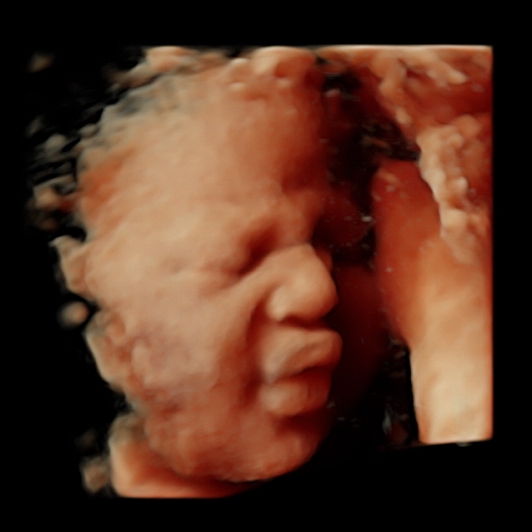

We have the latest ultrasound technology (HD Live) available. We provide you with the clearest 4d ultrasound images and nothing is left to the imagination, here is a reality, you will see your baby's movements in real time. We have some of our babies' images in our gallery so you might look according to your gestational age and get an idea of how you will see your baby. Please scroll down this page for more samples of our before and after baby pictures. They will give you a better idea of what are you getting when you book a 3D/4D/HD Live ultrasound session with Preggoland. We cannot wait to enjoy this unforgettable experience with you!

27 to 33-34 Weeks

Graphical explanation of how the babies are looking according to the gestational age. All 2D, 4D & HD Live images featured here have been taken by Preggoland. Please use them as a reference for your booking, from 12 weeks of pregnancy to 18/19 you can get beautiful full-body pictures & videos, your tiny human is growing fast. Don’t miss the opportunity to watch your baby’s development.